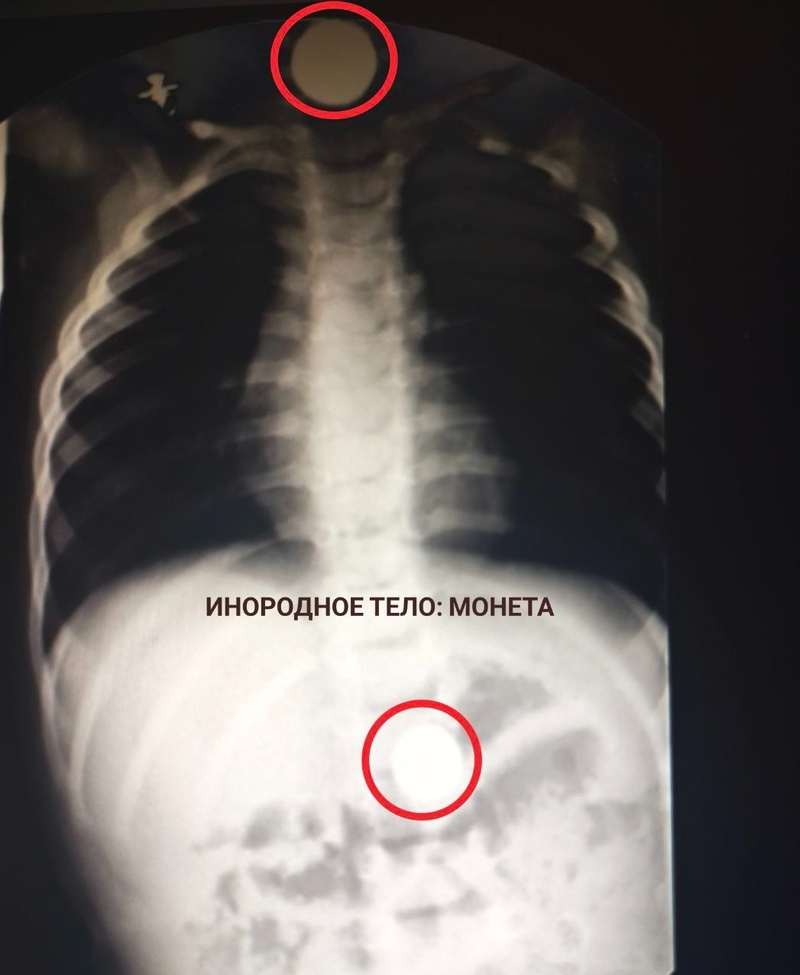

«Ежегодно в ГКБ Пятигорска поступают десятки пациентов с инородными телами. Среди них немало детей. И им, как правило, требуется экстренная медицинская помощь»,

— рассказали медики.